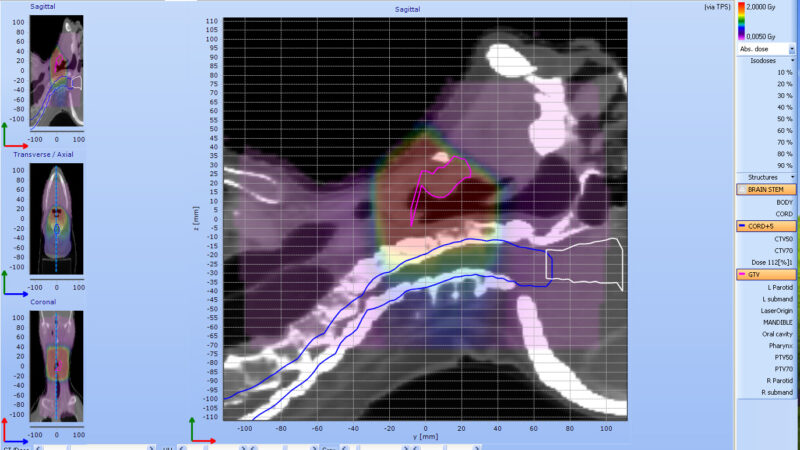

With the Delta4DVH Anatomy software option, you can verify and analyze the dose that has been delivered to the patient anatomy. Based on the measurements in the isocentric target region and dose calculation of the dose in the patient anatomy you now have a truly independent verification of the delivered dose.

Analyze the dose delivered to the patient anatomy